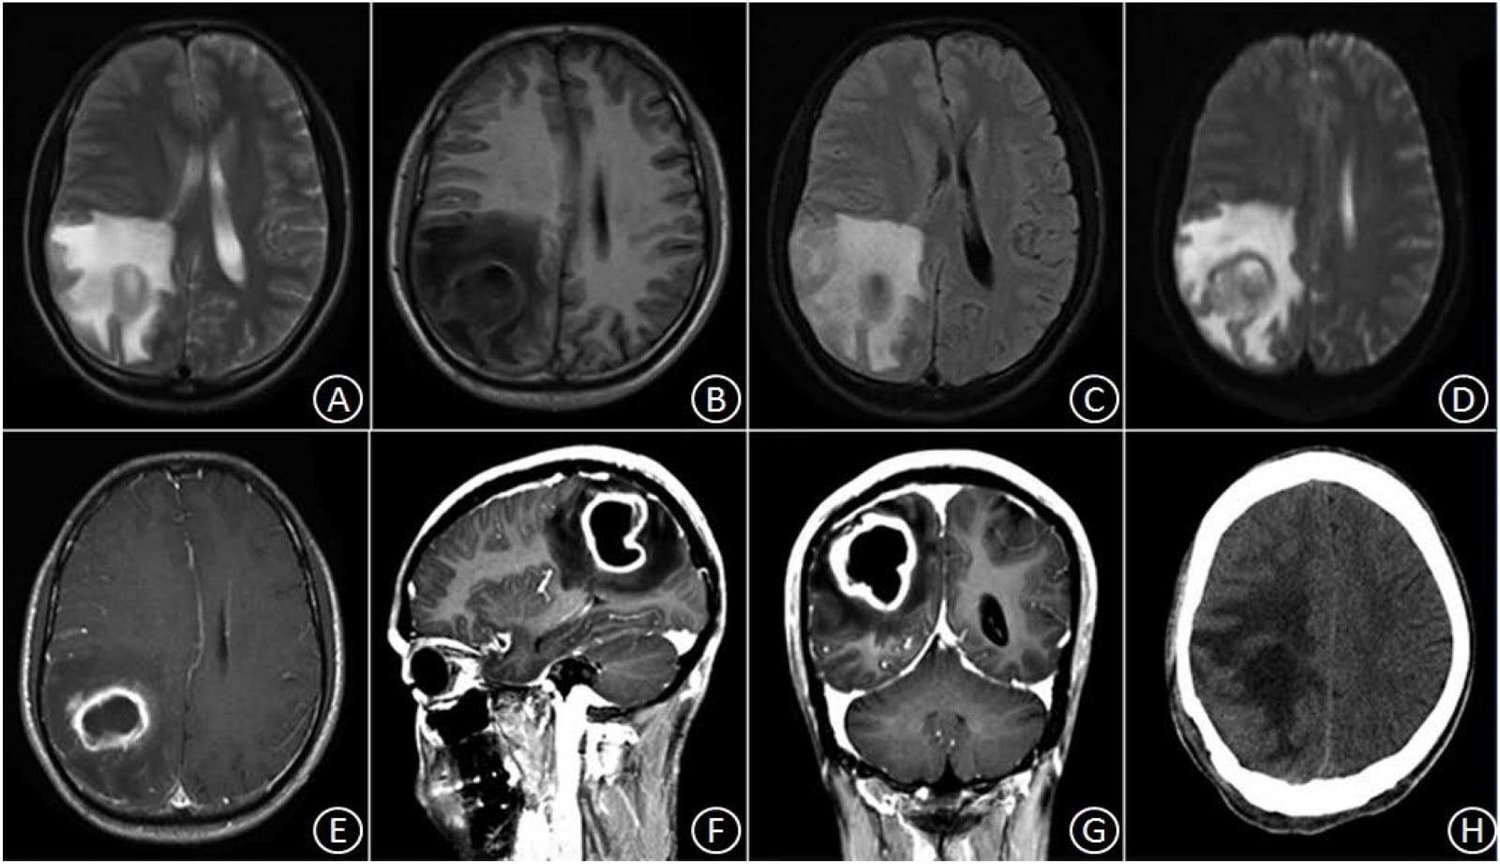

وحسب المركز ، فان خراجات الدماغ؛ حتى في هذه الأعداد المرتفعة نادرة نسبيًا، لكنها أيضًا خطيرة جدًا. مشددا «إنها عدوى في الدماغ ناتجة عن البكتيريا أو الفطريات التي تدخل المخ؛ عادةً إما عن طريق مجرى الدم من عدوى في جزء آخر من الجسم، مثل الالتهاب الرئوي أو من خلال عدوى في الرأس، مثل الأذنين والأسنان أو الجيوب الأنفية. إذ يمكن لهذه الجيوب المليئة بالصديد أن تمارس ضغطًا على أنسجة المخ حولها وتقطع تدفق الدم. كما يمكن أن تسبب الخراجات تلفًا في الدماغ. وفي الحالات الشديدة، يمكن أن تكون قاتلة؛ لذلك تحتاج إلى علاج سريع إلى حد ما بالمضادات الحيوية. وفي بعض الحالات بالجراحة»، وذلك وفق ما نشر موقع «ساينس إليرت» العلمي المتخصص، نقلا عن Johns Hopkins Medicine.